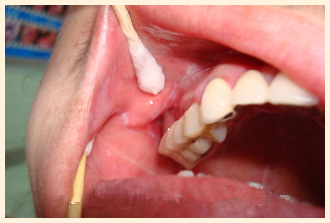

李先生,一名退休公务员,患口腔扁平苔藓多年, 唇部内侧黏膜常呈白色的圆或椭圆形斑块,表面可见白色网状损害硬,常..... 【详细】